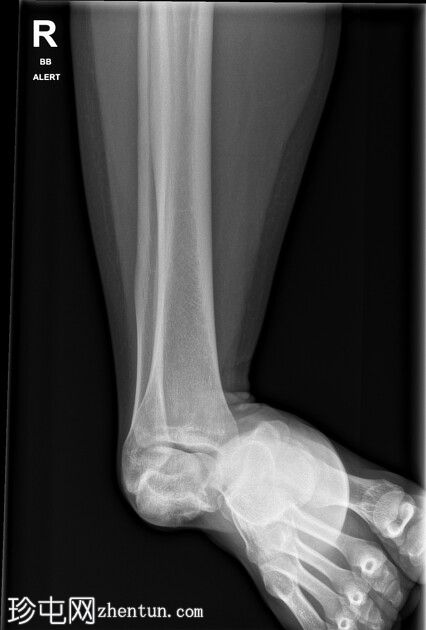

创伤室仅有单侧正位片。距下骨外侧脱位。未发现骨折。

最初远端脉搏消失。在急诊科镇静下成功复位,远端脉搏恢复。CTA(未提供)显示动脉造影良好,无血管损伤,距骨后突内侧轻微粉碎性骨折。